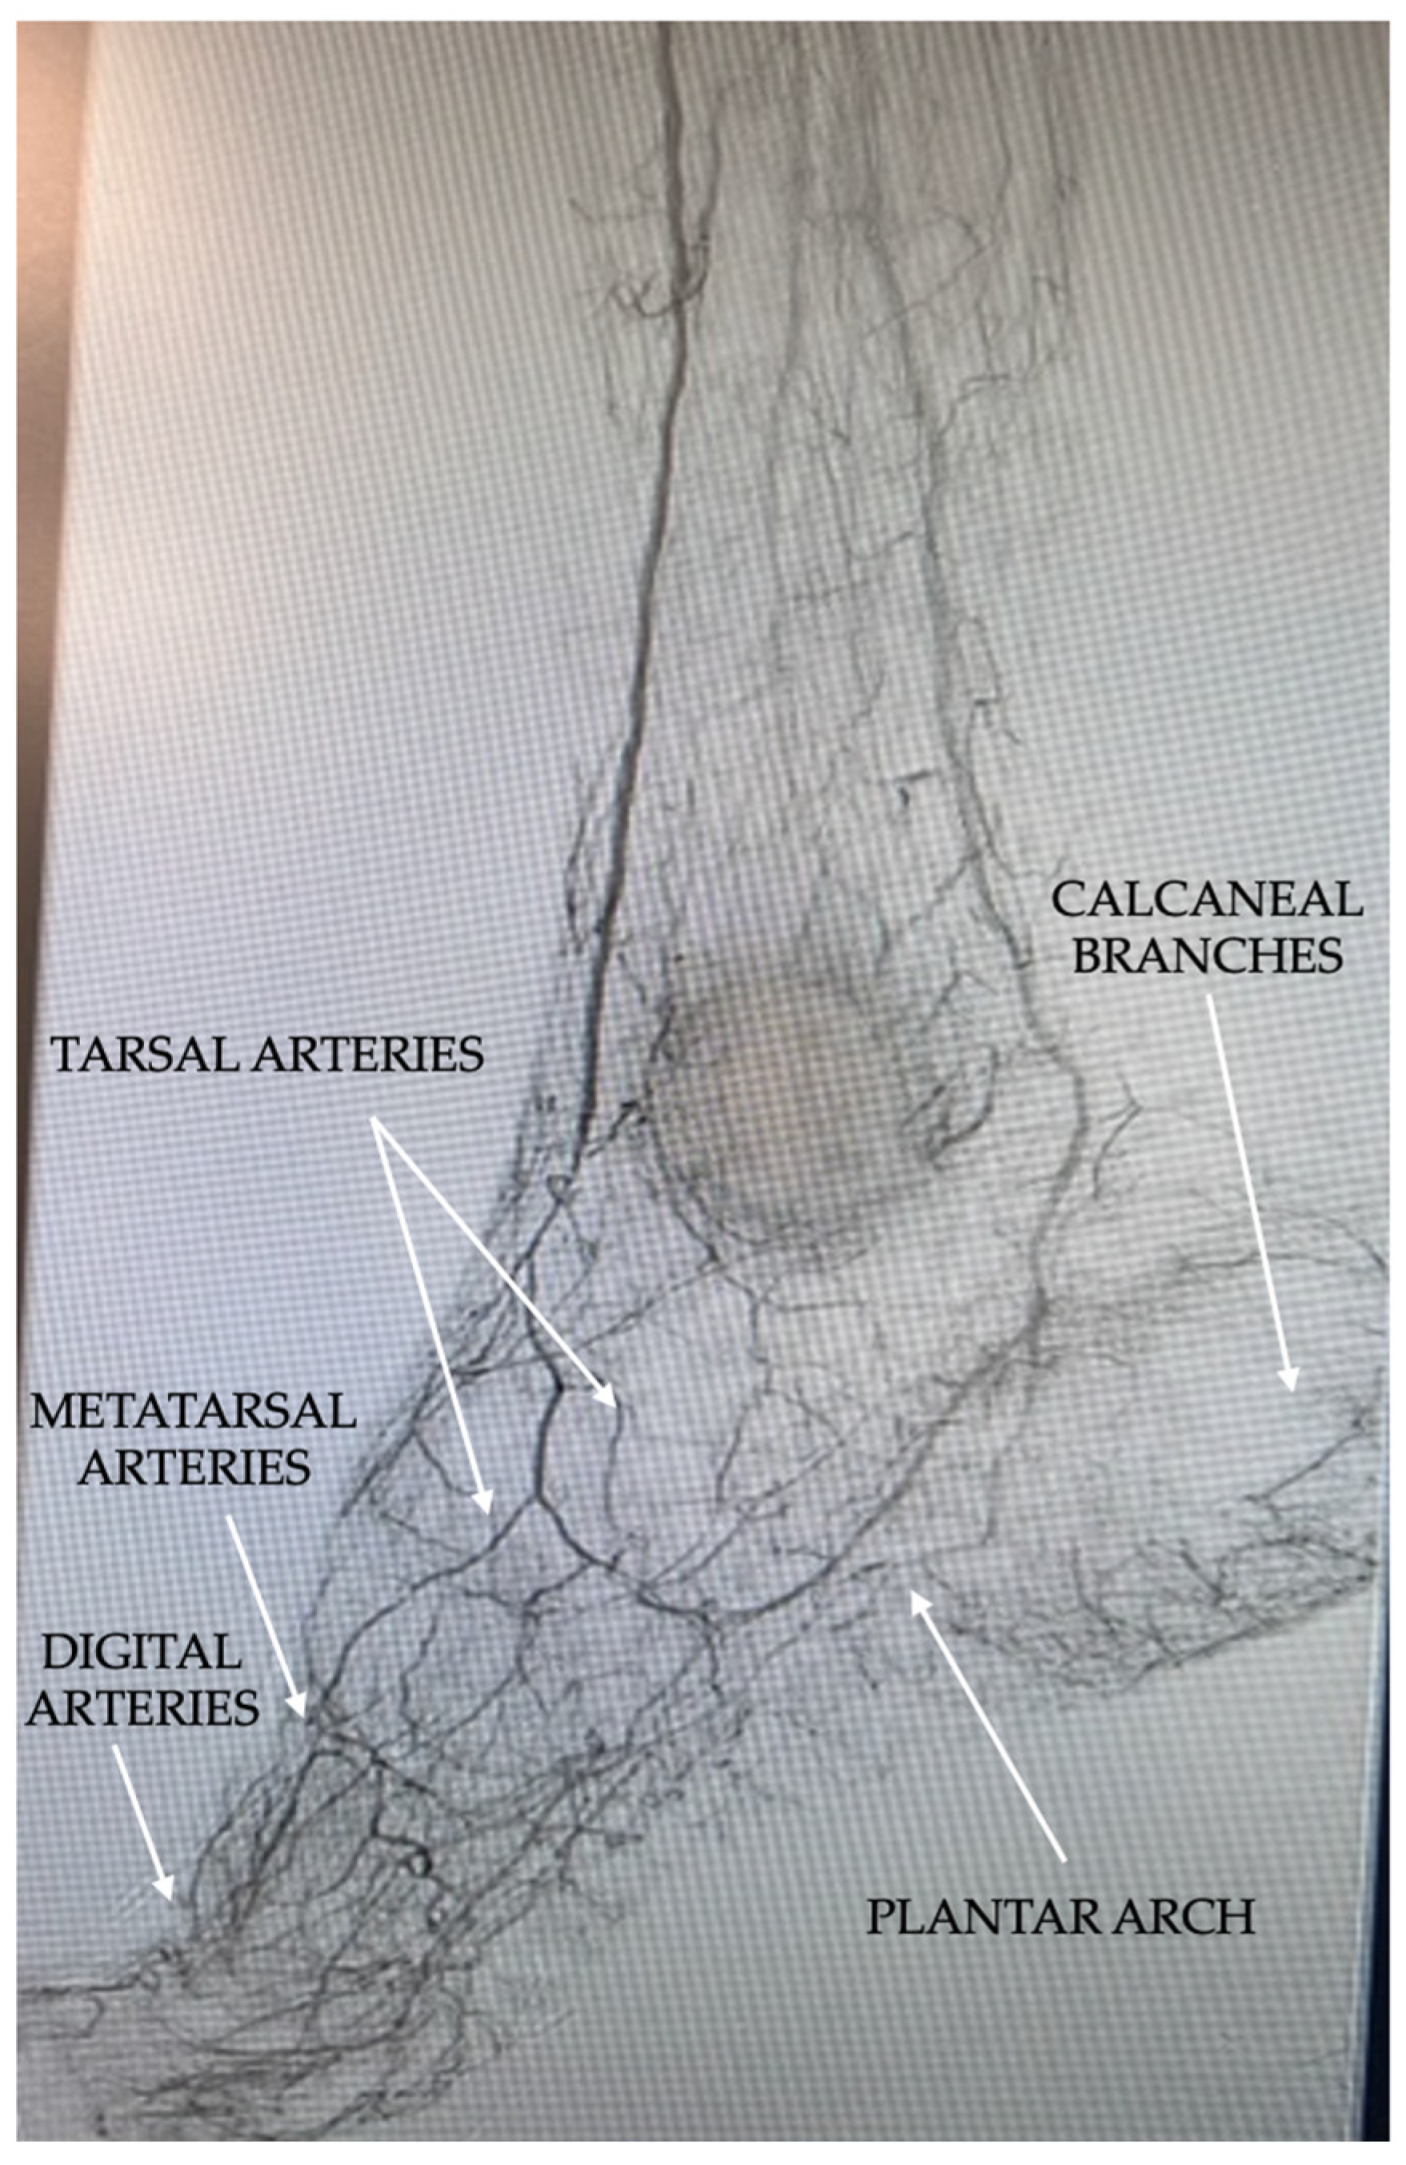

- Ferraresi, R.; Mauri, G.; Losurdo, F.; Troisi, N.; Brancaccio, D.; Caravaggi, C.; Neri, L. BAD transmission and SAD distribution: A new scenario for critical limb ischemia. J. Cardiovasc. Surg. 2018, 59, 655–664. [Google Scholar] [CrossRef] [PubMed]

- Meloni, M.; Izzo, V.; Giurato, L.; Gandini, R.; Uccioli, L. Below-the-ankle arterial disease severely impairs the outcomes of diabetic patients with ischemic foot ulcers. Diabetes Res. Clin. Pract. 2019, 152, 9–15. [Google Scholar] [CrossRef] [PubMed]

- Nakama, T.; Watanabe, N.; Haraguchi, T.; Sakamoto, H.; Kamoi, D.; Tsubakimoto, Y.; Ogata, K.; Satoh, K.; Urasawa, K.; Andoh, H.; et al. Clinical outcomes of pedal artery angioplasty for patients with ischemic wounds: Results from the multicenter RENDEZVOUS registry. JACC Cardiovasc. Interv. 2017, 10, 79–90. [Google Scholar] [CrossRef]

- Palena, L.M.; Brocco, E.; Manzi, M. The clinical utility of below-the-ankle angioplasty using “transmetatarsal artery access” in complex cases of CLI. Catheter. Cardiovasc. Interv. 2014, 83, 123–129. [Google Scholar] [CrossRef] [PubMed]